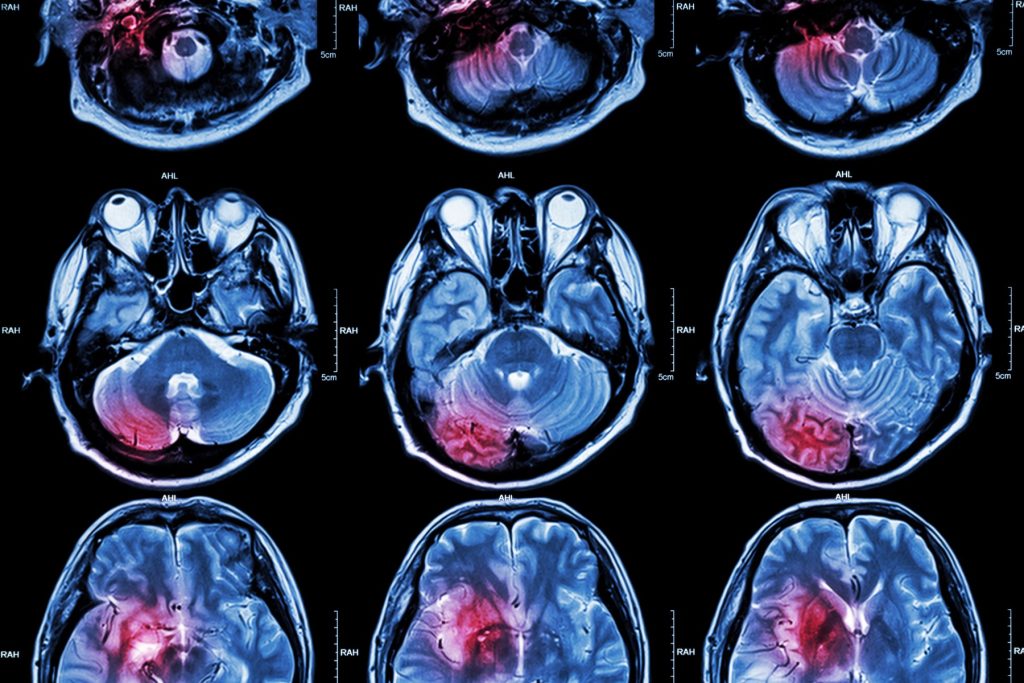

A powerful magnetic field and radio waves are used in magnetic resonance imaging, or MRI, to provide finely detailed pictures of the body’s interior components. American Heart center in Dubai offers MRI in Dubai provide high-quality imaging for precise diagnosis and treatment preparation.

- Brain